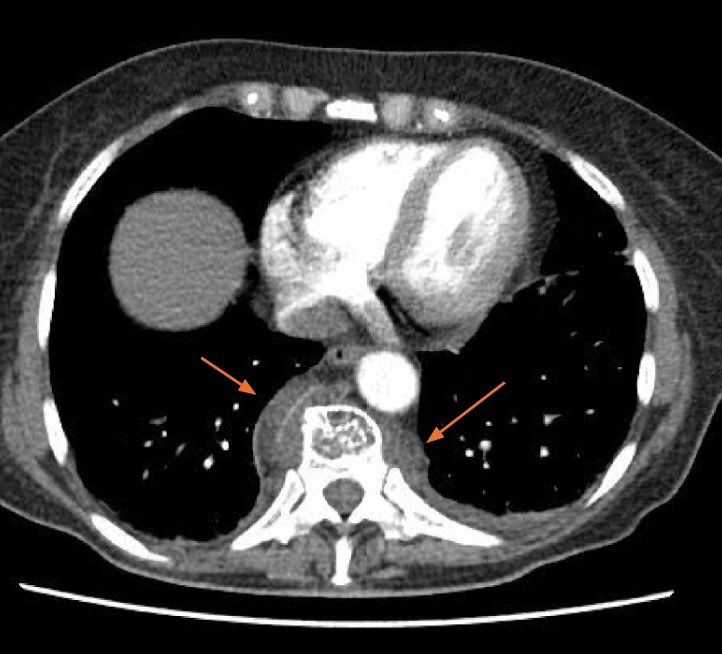

Eine CT-Thorax-Untersuchung wurde zum Ausschluss einer Lungenarterienembolie bei Dyspnoe veranlasst. Diese zeigt erweiterte knöcherne Markräume und extra-medulläre Hämatopoese (EMH) entlang der Wirbelsäule, insbesondere im paravertebralen Bereich (Pfeile). Diese extra-medulläre Hämatopoese tritt als weichteildichte Raumforderung auf, die entlang der Rippenmuskulatur und teilweise im posterioren Mediastinum zu sehen ist. Die Ultraschalluntersuchung des Abdomens zeigte eine Splenomegalie (Pol-zu-Pol Abstand von ca. 21 cm)